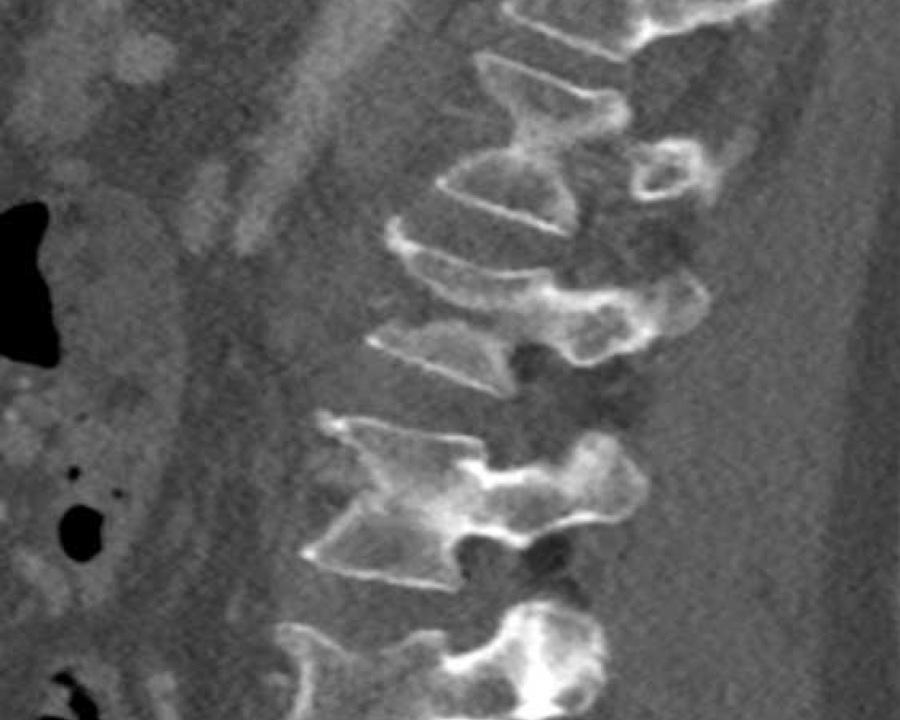

Type B / Distraction injuries

B3 Extension distraction injury

Hyperextension can result in distraction of the anterior tension band, which is formed by the vertebral bodies, the anterior and posterior longitudinal ligaments and the intervertebral disc.

These injuries can be difficult to detect since patients are scanned in the supine position laying on their back, which may obscure the anterior distraction.

However, these injuries mainly occur in patients with a rigid spine as a result of osteoarthritis, DISH or Ankylosing Spondylitis (SpA).

Stay persistent when examining a patient with a rigid spine until you have found the B3 injury.

Extension distraction is characterized by:

- Distraction of the tension band on the anterior side.

- Any horizontal or oblique fracture line through vertebral bodies anteriorly with separation on both sides.

- Widening of intervertebral disc space.

Scroll through images.

What are the findings?

Findings

- C injury? No.

- Signs of a rigid spine?

Yes, so be aware of potentially very subtle B3 injury. - A subtle fracture on the anterior vertebral body is seen (arrows).

Conclusion

Injury type B3.